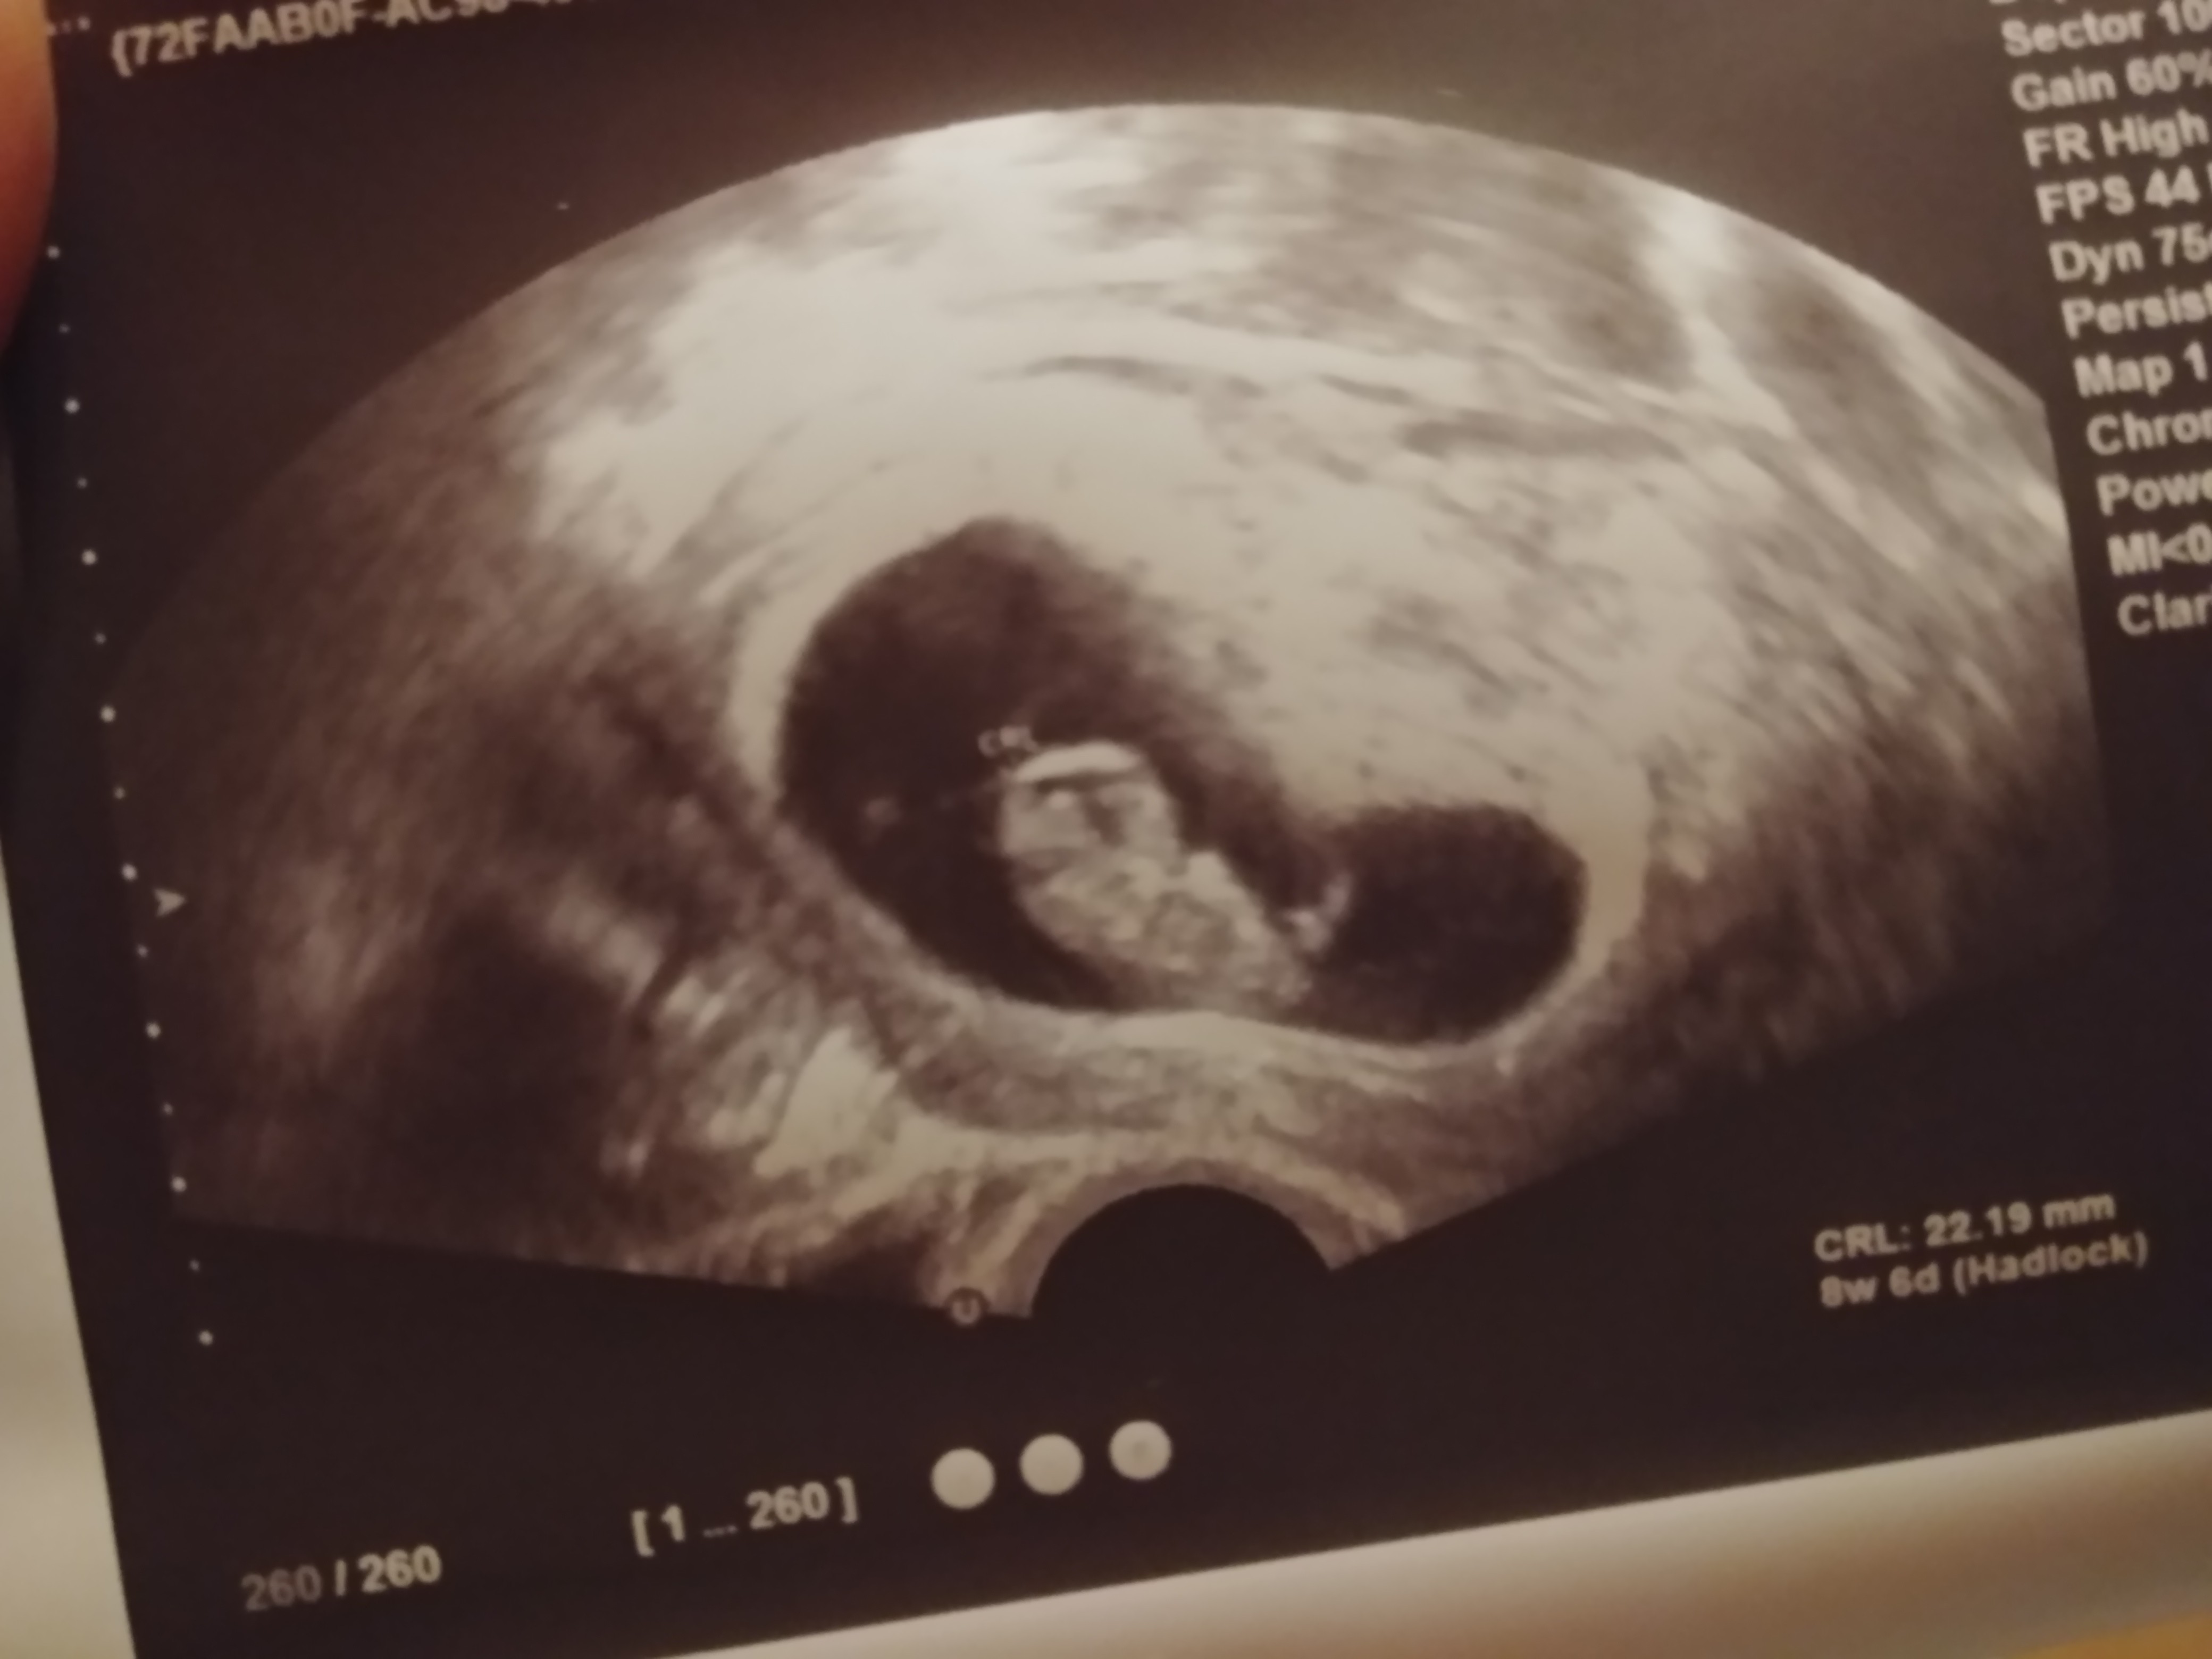

To i ja wkleję swoje szczęście:

F454A06C-499E-4798-9DCB-321BA9A04C0B.jpeg